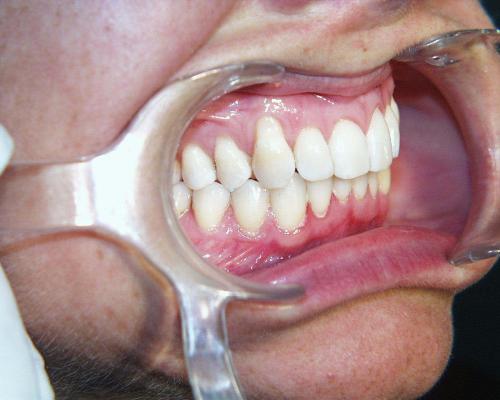

Während der Behandlung

Fallbeispiel 4 zeigt einen häufigen Befund bei erwachsenen Patienten: Die Stellung der Schneidezähne hat sich in beiden Zahnbögen im Laufe der Jahre erkennbar verschlechtert, und die Patienten fühlen sich dadurch zunehmend beeinträchtigt. Die in diesem Beispiel nur geringgradigen Abweichungen im Oberkiefer ließen sich mit nahezu unsichtbaren, herausnehmbaren Alignerschienen behandeln, während die Korrektur der stärkeren Schachtelstellung der unteren Frontzähne eine festsitzende Zahnspange erforderte. Auch hier ist nach der Korrektur die Verwendung innenliegender aufgeklebter Stabilisierungsdrähte über viele Jahre hinweg ratsam.